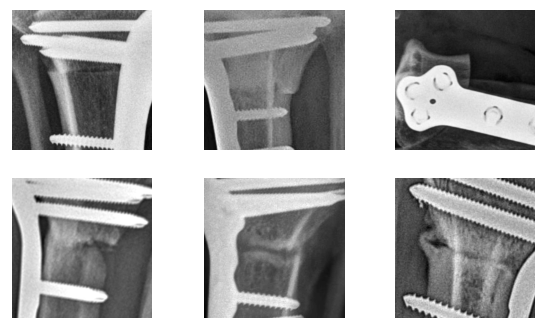

To obtain a more holistic understanding of model performance, we use 6 major visual features identified during data analysis as a guide for understanding the model’s decision-making process. Figure 5 displays the performance of the clustering system on example-saliency crops with each one of the major visual features.

All of the saliency crops selected as representative of vertical lines were assigned by the KNN to cluster 2, and all the horizontal lines to cluster 5, along with most oblique lines. Interestingly, different views of medical devices appear to be clustered separately, with frontal views of the plate found in cluster 3 and crops containing the screws in cluster 0. The zoomed out crops, which mostly represent aberrant mistakes, are found in cluster 4. Finally, the crops without lines are mostly found in cluster 1.